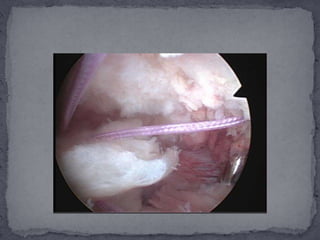

Bursa fibrotica e inflamada.http://3.bp.blogspot.com/_JgiBXPNvNYI/SDDxrMaIoFI/AAAAAAAAAIA/sz82lBQYSSQ/s1600-h/001.jpg

Resección de bursa.http://4.bp.blogspot.com/_JgiBXPNvNYI/SDDx1caIoGI/AAAAAAAAAII/Fd2DBmtND-s/s1600-h/002.jpg

Bursa fibrotica einflamada.http://3.bp.blogspot.com/_JgiBXPNvNYI/SDDxrMaIoFI/AAAAAAAAAIA/sz82lBQYSSQ/s1600-h/001.jpg